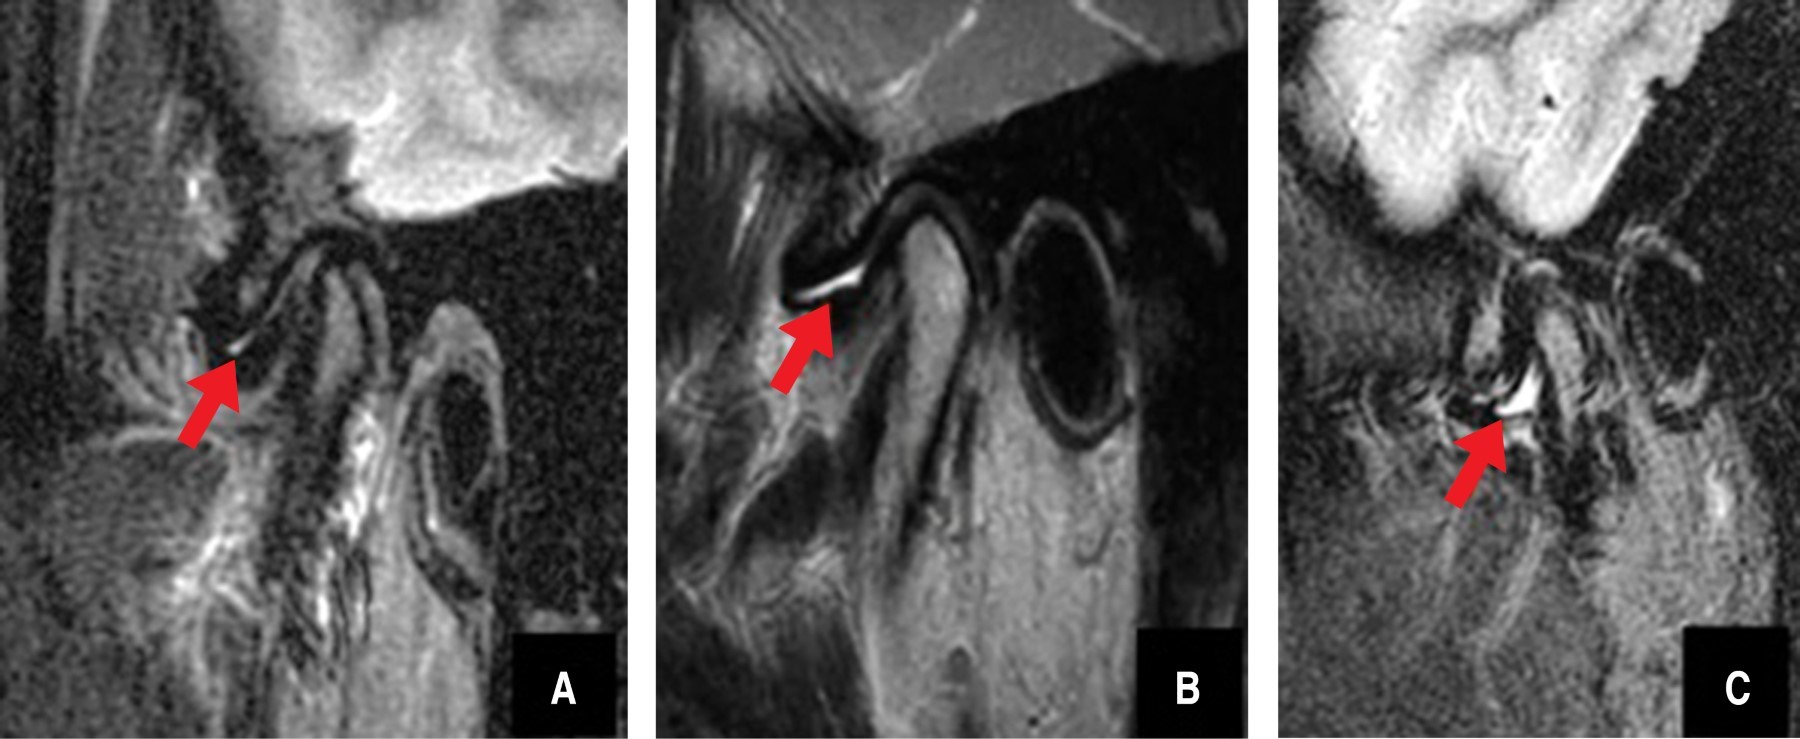

Figure 2